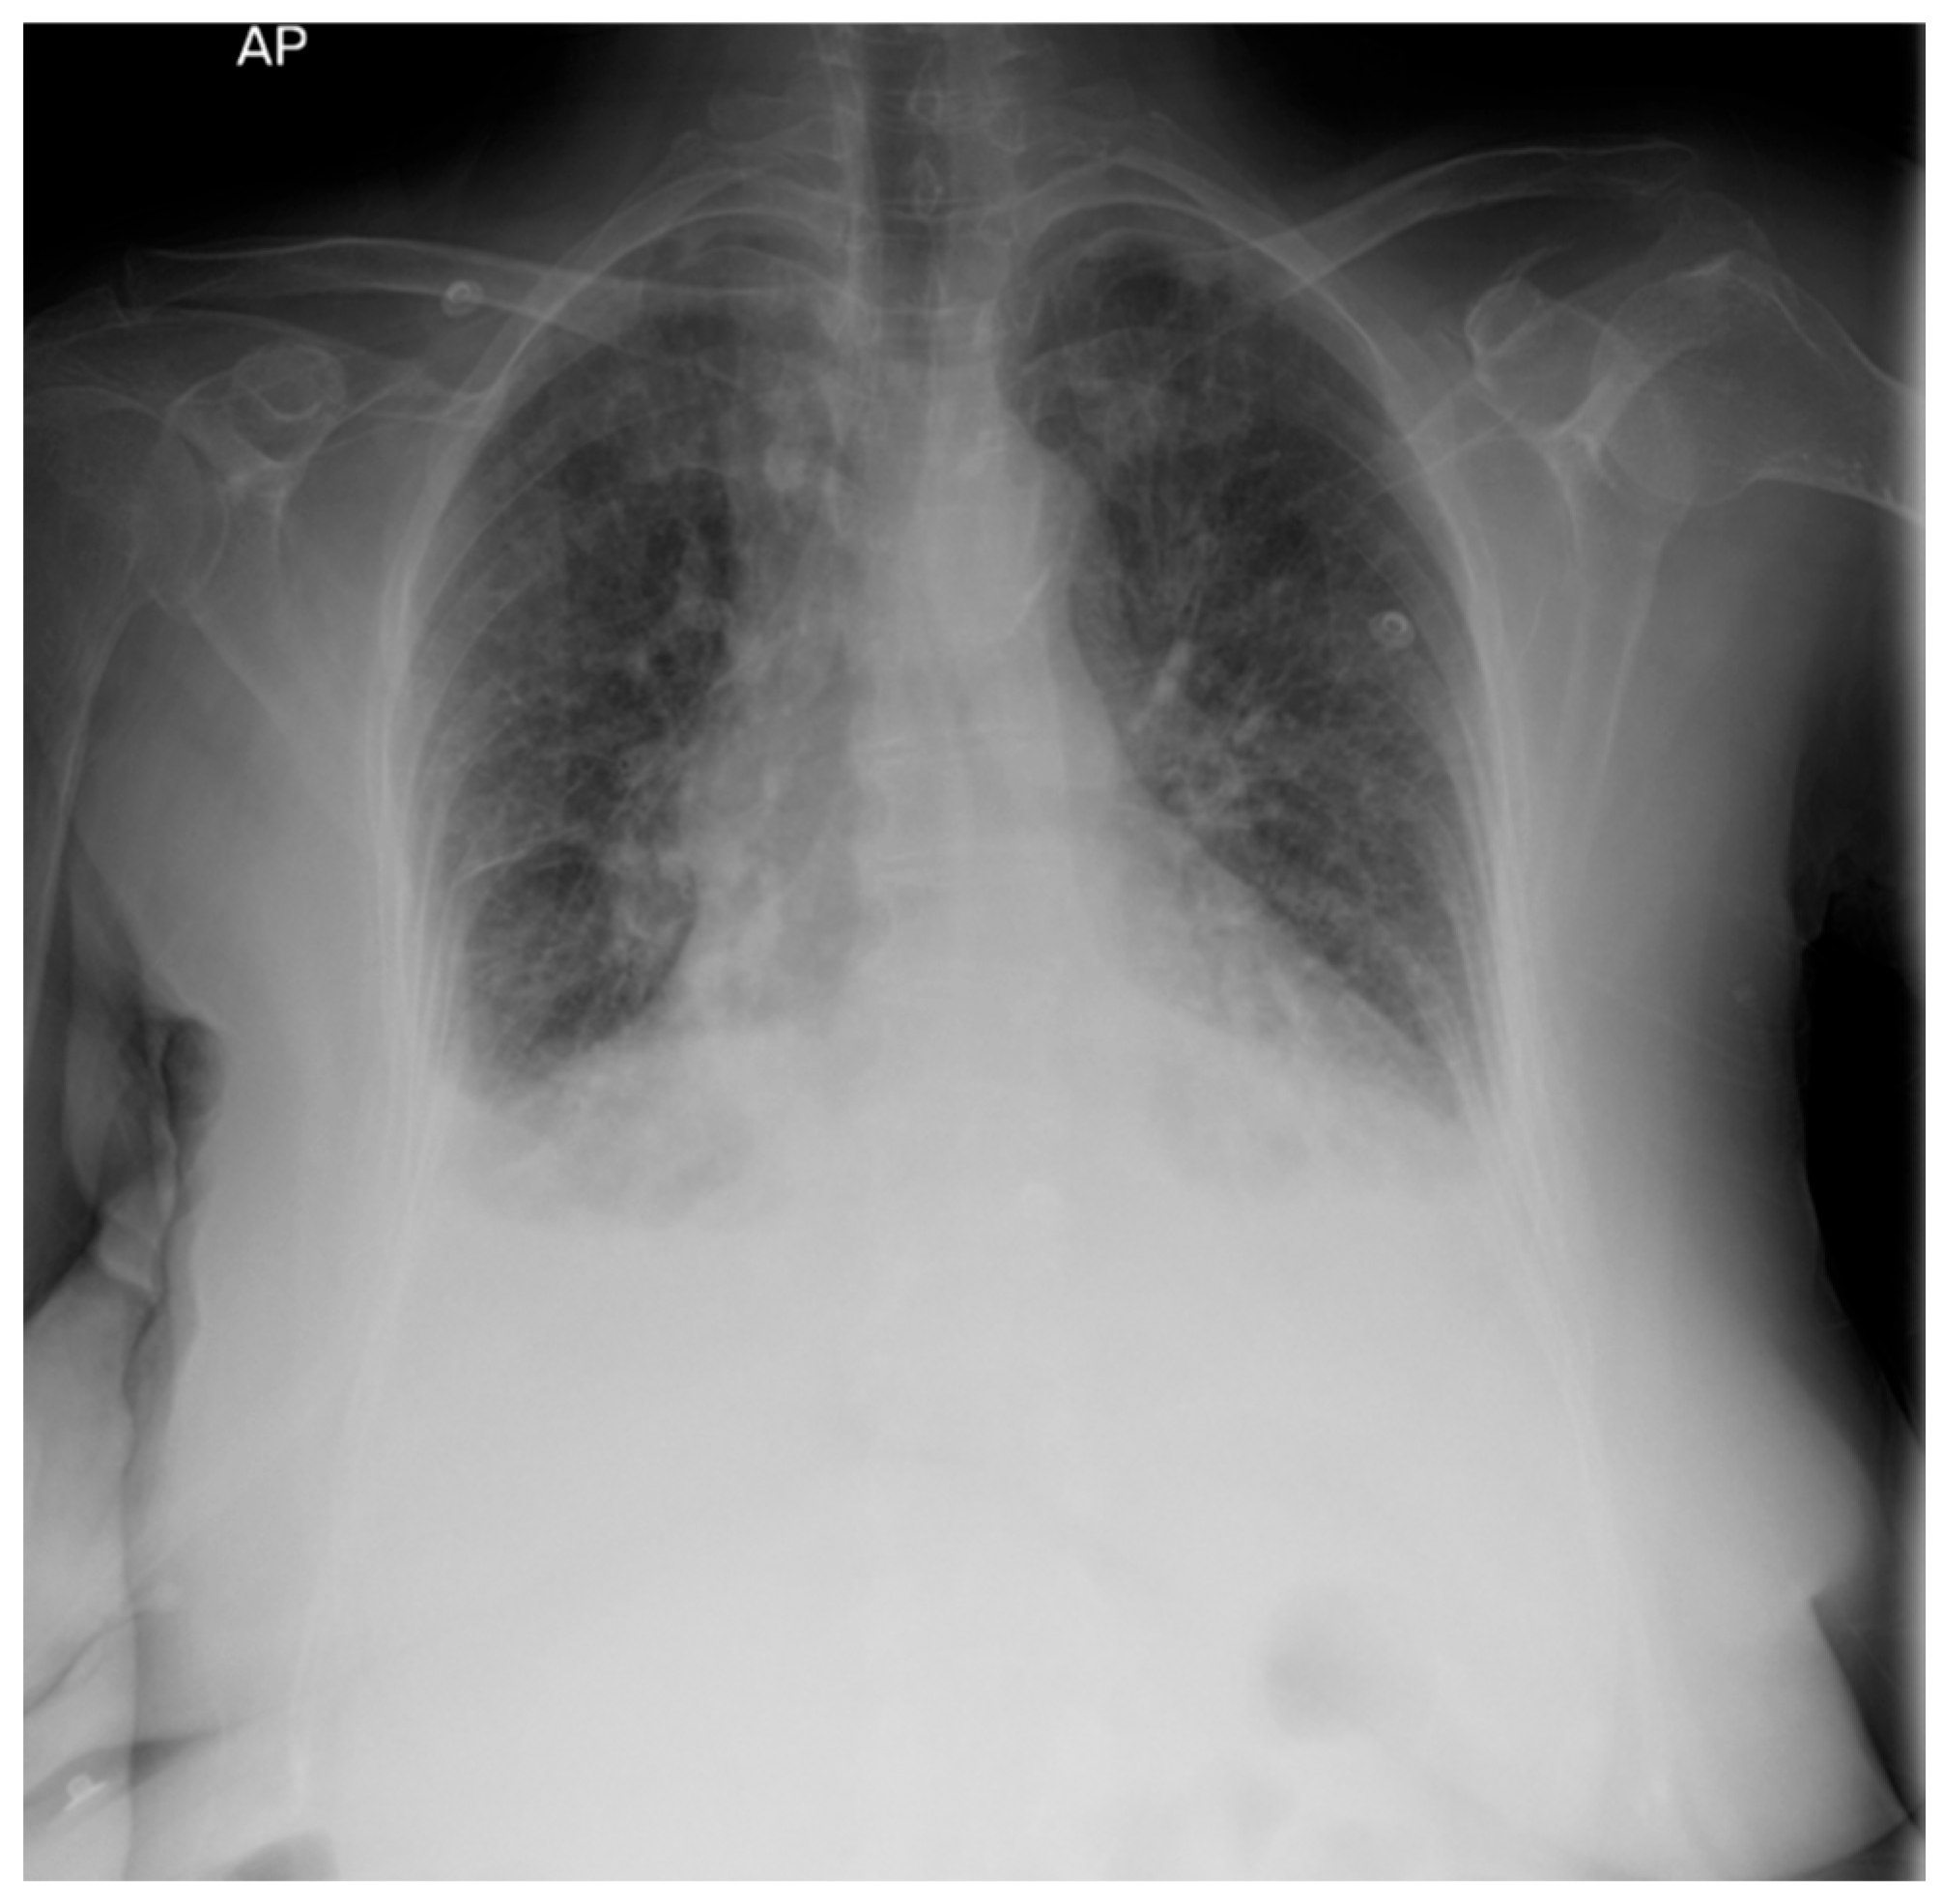

2. Case Presentation